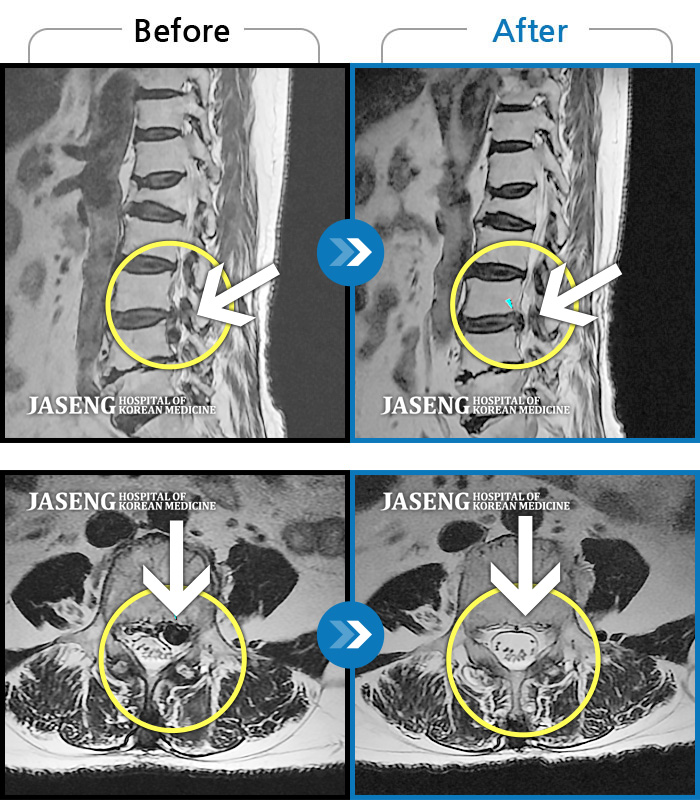

허리디스크

보라매 · 왕오호 원장

좌측 허리 통증과 좌측 다리 저림

촬영시기

2017.08.26 ~ 2018.08.21

2018.12.28

조회수 177